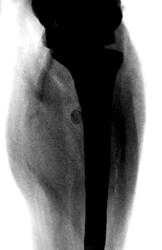

Пациентка направлена на рентгенографию костей предплечья.

Мягкотканное муфтообразное образование в/3 предплечья, с костями предплечья не связанное. Вызывает сомнение плотноинтенсивное округлое включение в мягких тканях по луче-ладонной поверхности на уровне верхней трети лучевой кости.

Мое мнение, судя по распространению мягкотканного образования от суставной капсулы локтевого сустава - синовиома. Относительно плотноинтенсивного включения ответить затрудняюсь.

У пациентки хорошо видимое опухолевидной образование, безболезненное. Пациентка отмечает, что данное образование заметила около 4- лет тому назад, и которое в последние два года значительно увеличилось в размерах. Жалобы у пациентки чисто косметического характера.

Скорее всего липома, есть просветление... Нельзя исключать липосаркому, раз быстрый рост...